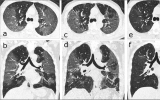

CT顯示三分之一的新冠肺炎患者可能終生肺部損傷

六個月后續CT掃描顯示,超過三分之一的康復患者具有肺部纖維化樣特征?,F在研究表明,這種后遺癥可能會在康復的患者中持續一生。 2021-01-29